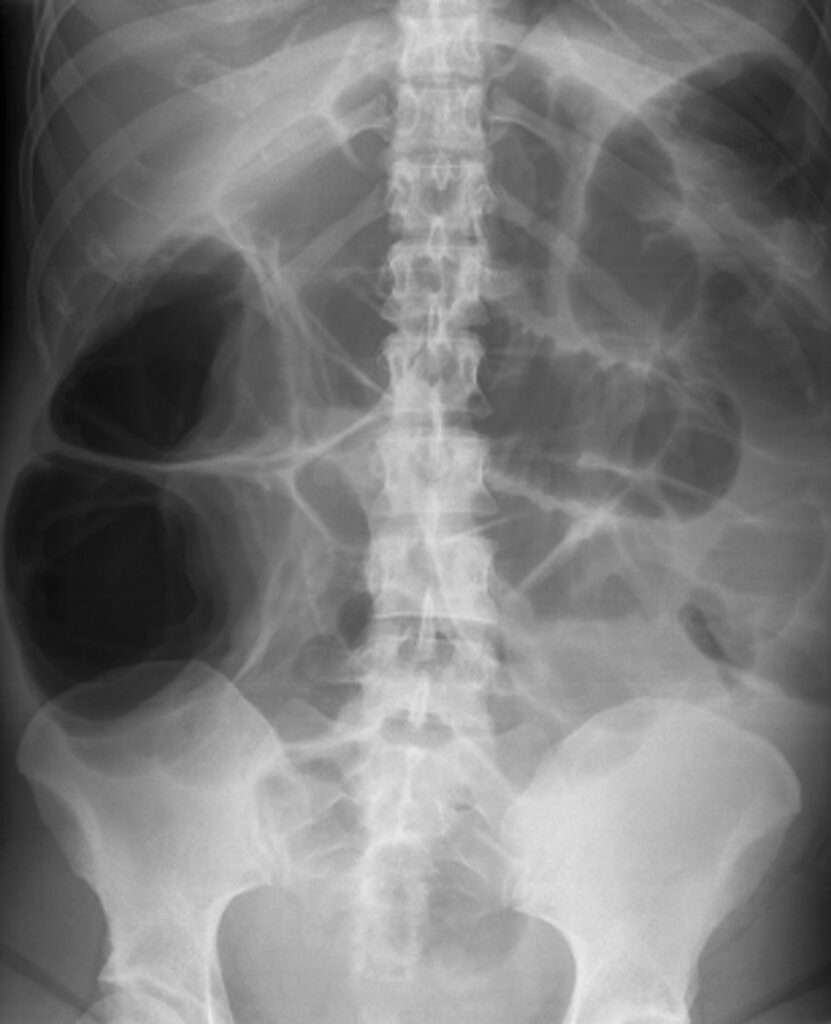

Pseudoobstrucción aguda del colon (síndrome de Ogilvie)

La dilatación masiva espontánea del ciego y del colon proximal es un fenómeno que puede presentarse en diversos contextos clínicos en pacientes hospitalizados, y es una condición que puede desencadenar…